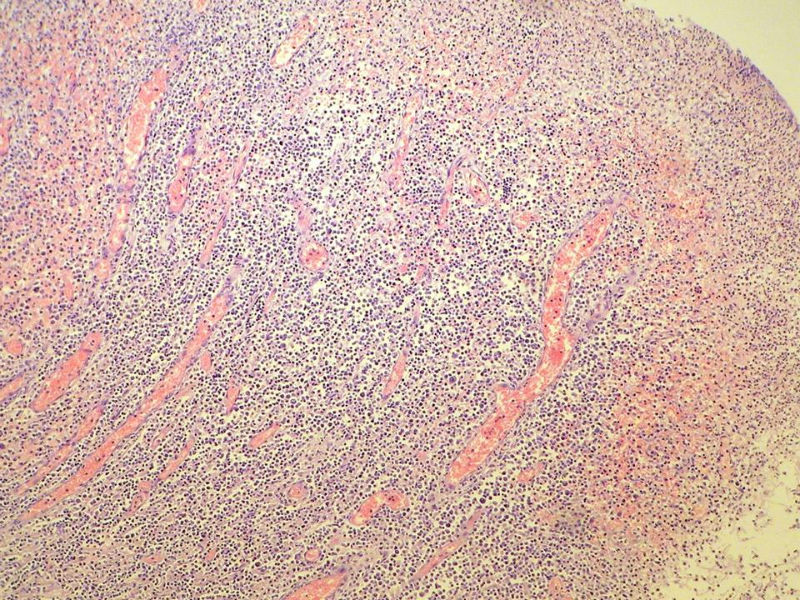

女,53岁,横结肠有9X6厘米大小溃疡,手术切除。

中老年人,溃疡很大,可见淋巴浆细胞样细胞弥漫浸润,散在大细胞,疑非霍奇颈淋巴瘤,倾向MALT伴浆样分化,不知是否破坏肌层?可否传肌层图?需IHC标记,鉴别淋巴瘤、腺癌及其它。

肉眼观仅是溃疡?有没有肠壁增厚、隆起?周围粘膜情况?肌层情况?有淋巴浆细胞样细胞、中心细胞,散在少量不成片的大细胞,不排除MALToma伴大细胞转化。

本例肉眼溃疡如溃疡性结肠炎,肠壁无明显增厚,表面辅以坏死,溃疡边缘稍隆起。镜下淋巴样细胞局限在粘膜层,肌层未见。谢谢!